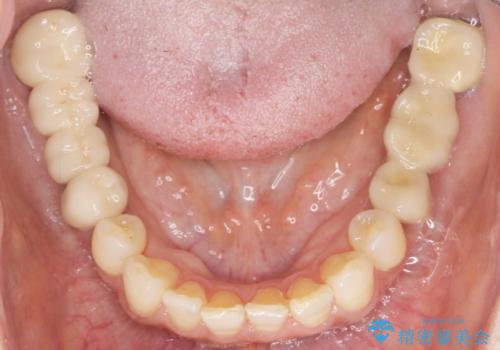

根管治療後、メタルボンドブリッジによる補綴治療を行いました。

自然な仕上がりと咬み心地に喜んで頂けました。

クラウンの種類:メタルボンドクラウン エコノミー